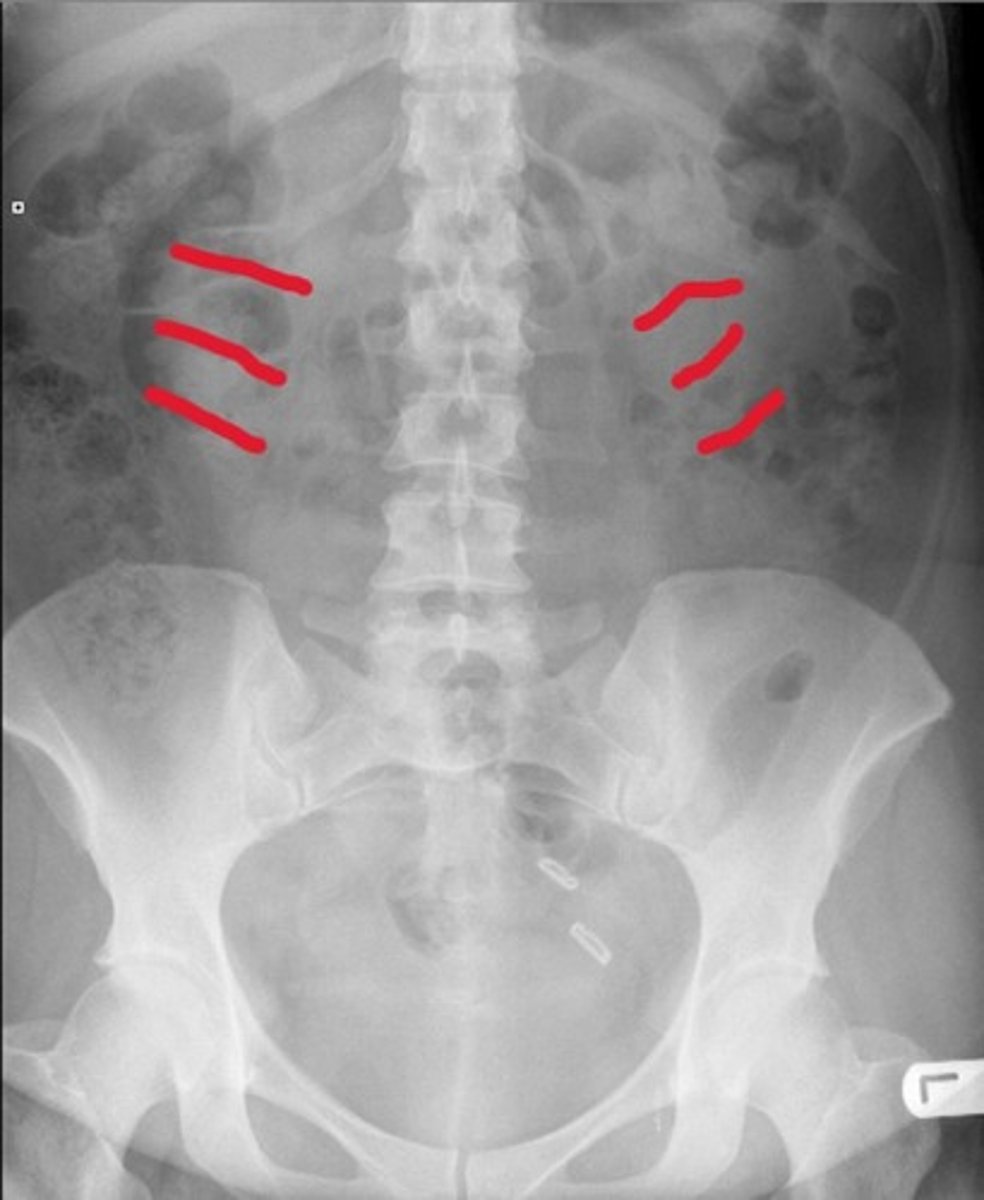

Psoas muscles

What are the red lines pointing to